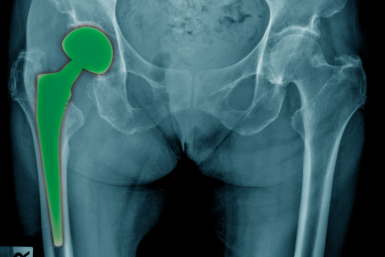

El ortopedista en Querétaro cuenta con la experiencia para ofrecer soluciones de mínima invasión hasta quirúrgicas según el tipo de lesión. Si el problema es leve, puede ser tratado con medicamentos o inyecciones articulares. Para lesiones deportivas o pinzamientos, se utiliza la artroscopia (cirugía mínimamente invasiva). Pero si la cadera ya está muy dañada por la artrosis, la mejor opción puede ser la prótesis de cadera.